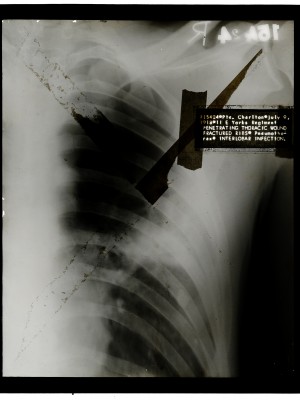

Ernst, Edwin Collection

Dr. Edwin Ernst, an only child born to St. Louis residents Charles and Catherine Ernst, was a notable Roentgenologist, a physician who specializes in radiological work. Dr. Ernst studied at Washington University in St. Louis and later at Moravian College in Bethlehem, Pennsylvania earning his advanced degrees. For two years he served as a resident physician at the St. Louis Mullanphy Hospital before leaving to pursue a private practice. When the United States formally entered the war in 1917, Ernst left St. Louis to become chief radiologist at Base Hospital 21. He was discharged honorably in 1919 with the citation of Major. His collection consist of x-ray images taken at Base Hospital 21 as well as drawings of radiological equipment and photographs.